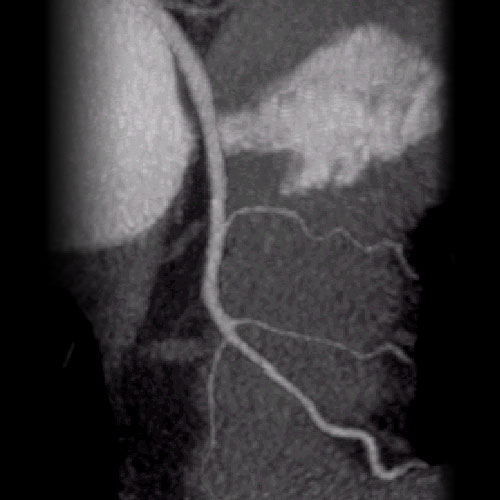

We utilize one of the few 64 slice CT scanners in North Texas that allows non-invasive diagnosis of such conditions as coronary artery disease (heart vessel blockage).  The heart vessels are displayed on our advanced 3D computer workstations where one of our doctors can make a diagnosis in minutes.  This procedure is much safer than cardiac catheterization.